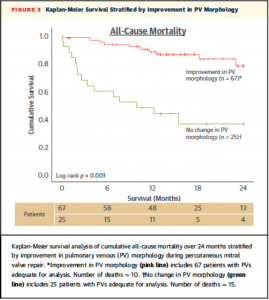

一方でPV flow波形が改善したか否かによる2群に分類したK-M curveでは術中にPV波形が改善した群において有意に生存率が高かった(Figure 3, Logrank P < 0.001) 。本文中には図は示されていないものの左房圧V波の改善や僧帽弁圧較差上昇(transmitral gradient ≥5 mmHg)について行ったK-M analysisでは有意な差を認めなかったとのこと。

(Figure 3)

(Figure 3)